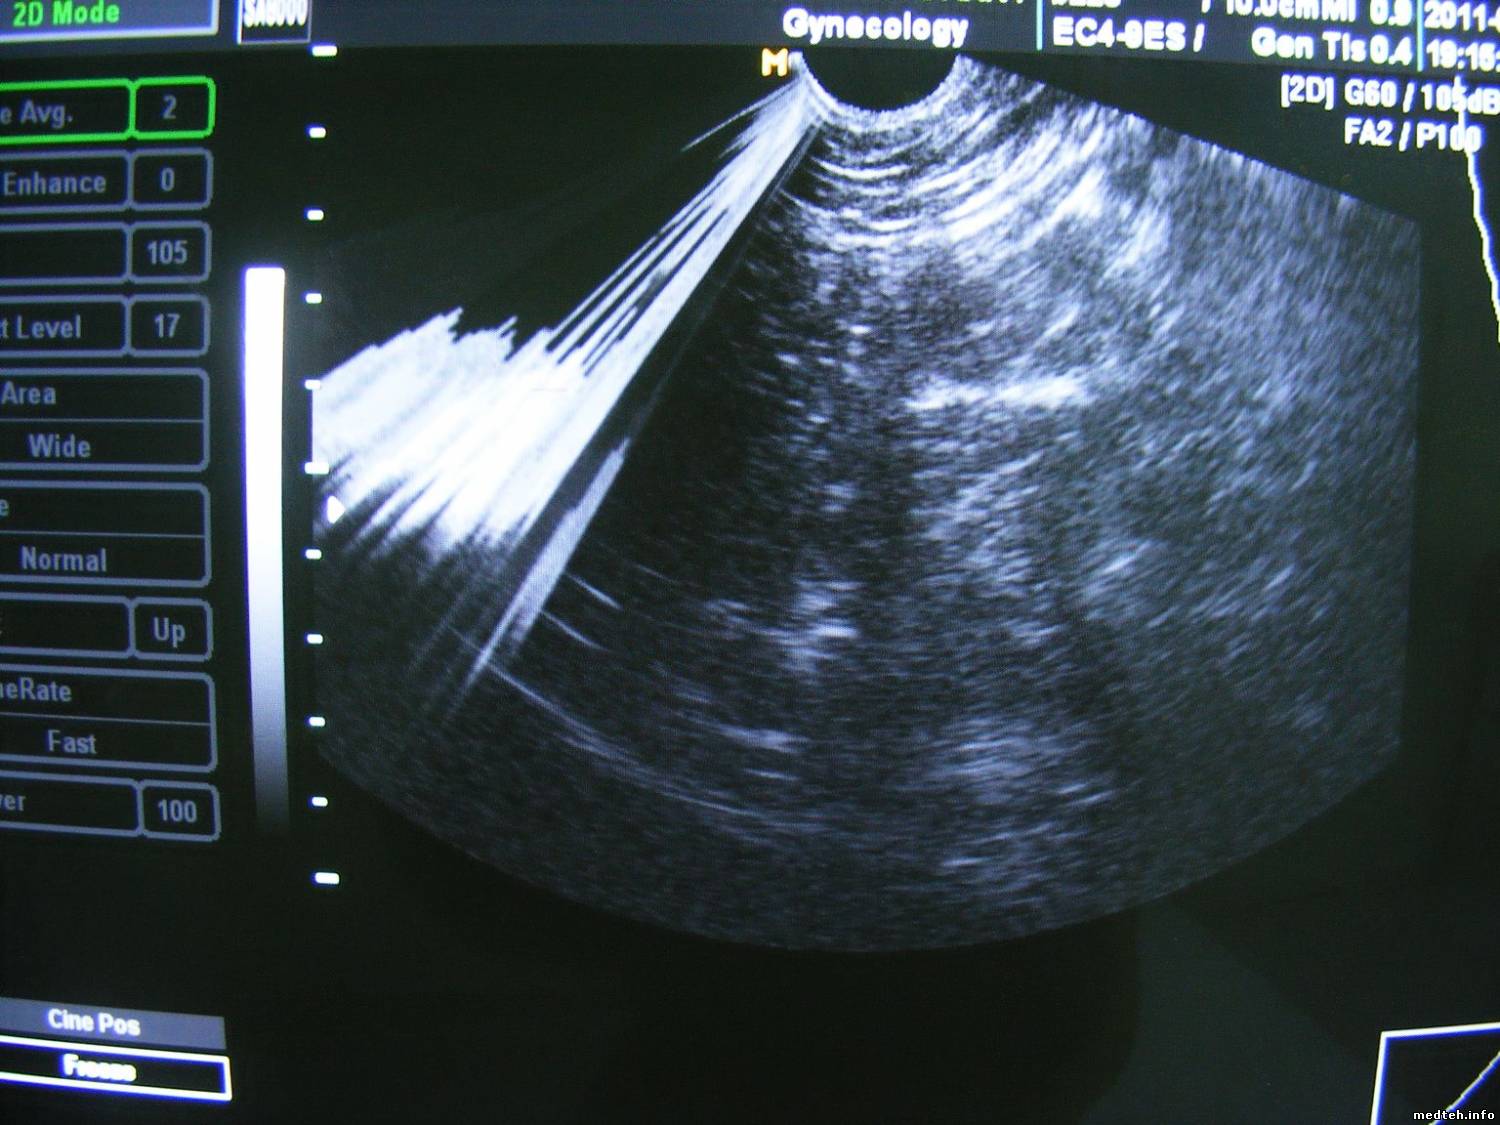

Помехи выглядят как показано на фото, фото сделано при работе с разными датчиками, одно фото когда стоит кардиологический датчик, другое фото, когда стоит гинекологичекий датчик.

3090305.jpg (164.8 Kb) · 1352311.jpg (68.7 Kb)

На фото где помеха более интенсивная сверху, работет кардиологический датчик, на фото где помеха слева идет к низу по всему полю сканирования работает гинекологичекий датчик.